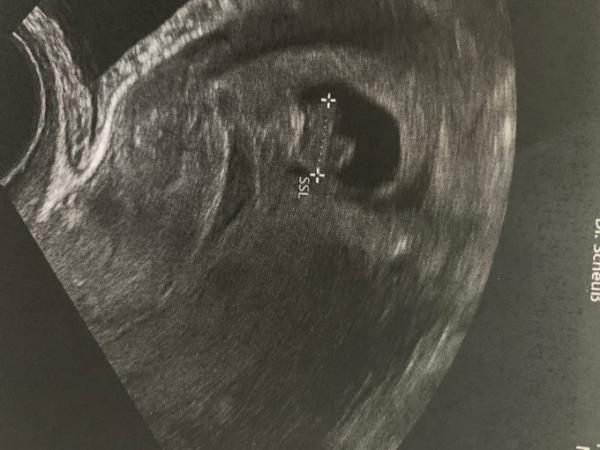

Hallo, ich hab seit dem 3.02 (Transfer+5 Blastozyste)Schmierblutung und seit dem 2 Blutstürze gehabt. In der Schwangerschaftswoche 7 waren die Blutungen, bei der ersten Blutung war im Krankenhaus eine intakte Schwangerschaft zu sehen mit Herzschlag. In der 8 SSW war ich jetzt in der KIWU sie hat auch eine intakte Schwangerschaft festgestellt, allerdings eine „Wasserstraße“ gesehen. Das heißt eine flüssige Blutstraße gesehen die raus läuft. Kennt das jemand? Hab ein Bild angehangen und rechts unter der Fruchthöle ist diese Straße zu sehen .

Hier das Bild